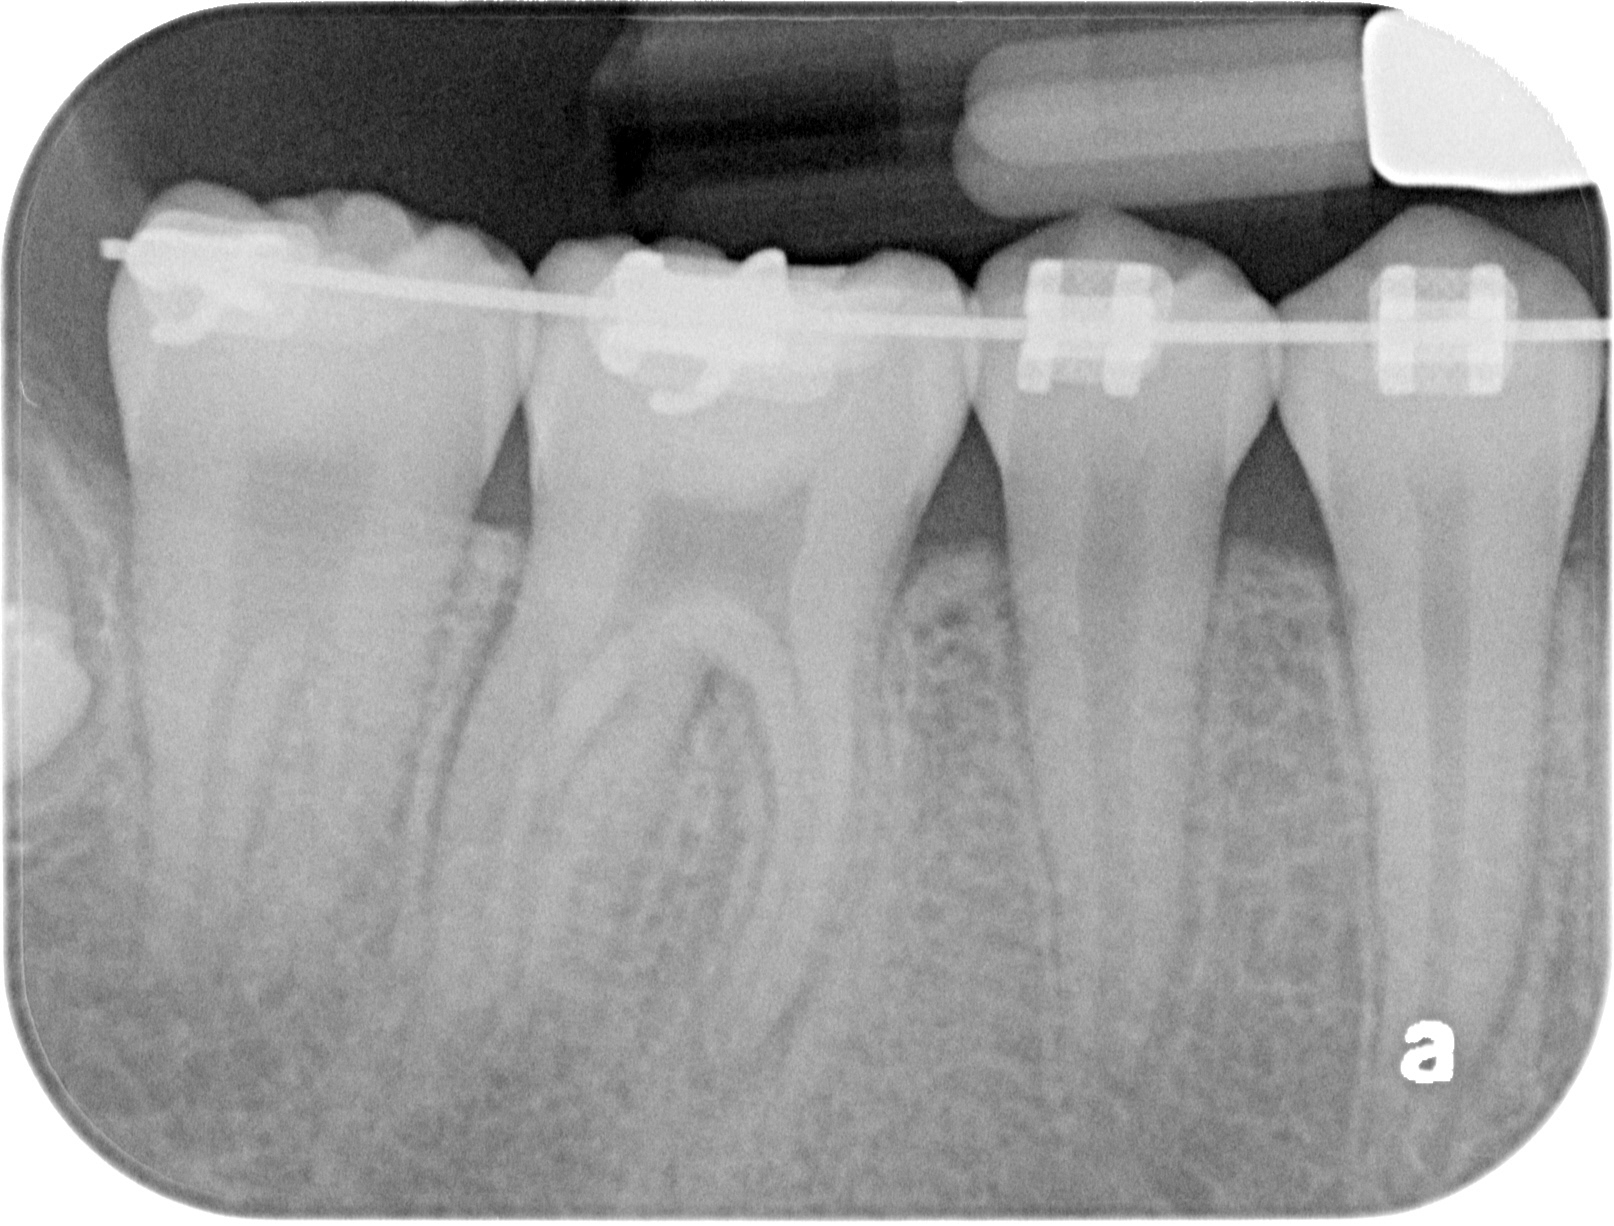

A 46 WITH 4 CANALS

INITIAL

FINAL